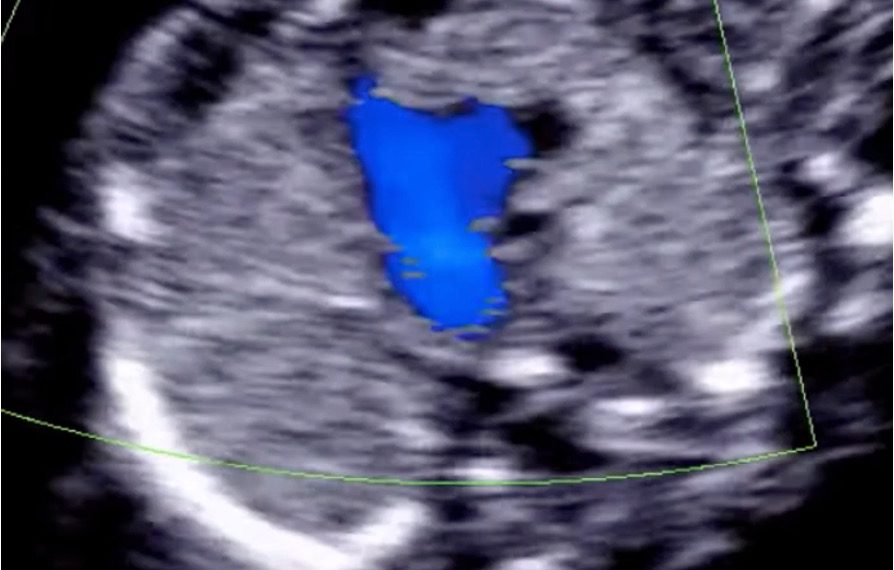

How To Do Aprile 2022: studio del cuore fetale nel primo trimestre

Cari soci, questo mese un nuovo video "How to do", sullo studio del cuore fetale nel primo trimestre